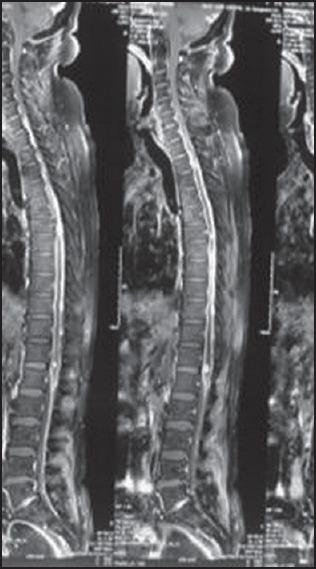

Figure 2.

Sagittal view showing leptomeningeal, extramedullary, and intramedullary metastasis

MRI of the brain was not suggestive of tumor at the primary site. Pre and postcontrast MRI of the spine showed a 24 mm × 9 mm × 11 mm ill-defined, enhancing, intramedullary lesion at D2-3 with cord expansion with extension into the extramedullary space with diffuse leptomeningeal involvement all along the cervical spine, along the filum and conus [Figures 2 and 3]. He underwent D2-6 laminectomy and tumor decompression, histopathology of which was suggestive of high grade astrocytoma compatible with recurrent metastatic glioblastoma (WHO grade IV). The patient then underwent radiotherapy which he could not tolerate and eventually succumbed to his disease after a period of 6 months.